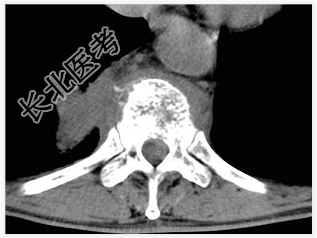

- [材料题] 男,32岁,低热、腰背痛,活动受限。

- 简答题1、结合CT检查,最可能的诊断是?

- 简答题4、椎体结核的治疗原则是什么?